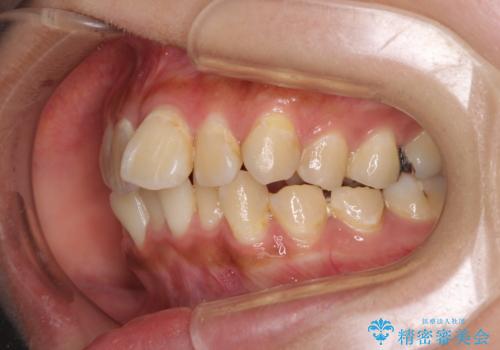

- 虫歯が多く、磨きにくい歯並びを改善したいとのことで来院された患者様です。

歯列は叢生が認められる程度でしたが、やや前突感があったので、少しでも口が閉じやすくなるように仕上げる方針としました。

神経を取り除かれている歯3本以外にも虫歯が認められたため、事前に処置を行い、インビザラインにて矯正治療を行うこととしました。

神経が取り除かれている歯は、クラウンによる補綴治療が必要であるため、矯正治療後にオールセラミッククラウンにて補綴治療を行うこととしました。

歯磨きしやすくなるとともに、飛び出していた前歯も引っ込めて整えることができました。